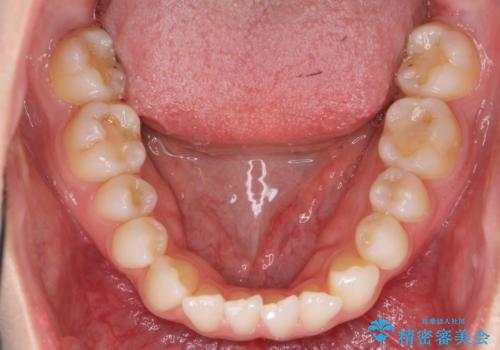

- 前歯のがたつきと小さな歯の形を治したいと来院。

前から2番目の歯が小さく、細くとがった形になっていました。

大きくしようにも、幅が少ない上に、また、内側に入ってしまっているため、矯正治療で前歯を並べてからセラミックでかぶせることにしました。

先に矯正治療をすることで、下の前歯を内側に入れることができ、上の歯のセラミックの幅や厚みを取ることができました。